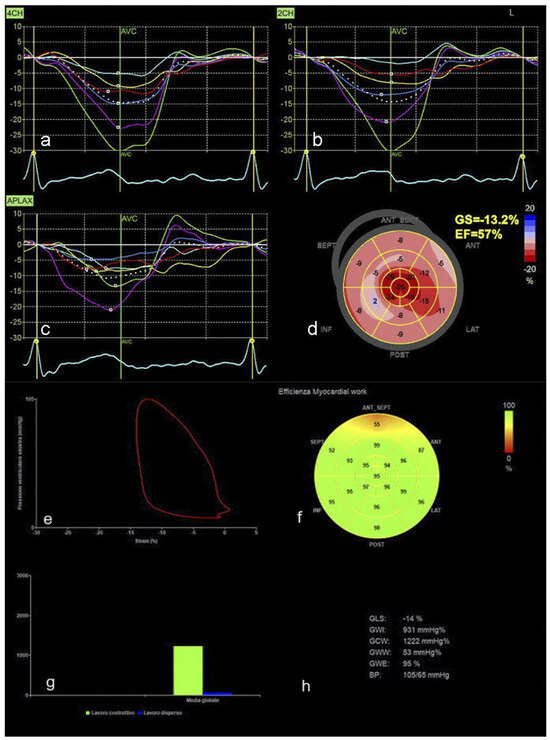

Cardiac Imaging Evolution: Artificial Intelligence-Guided Advancement